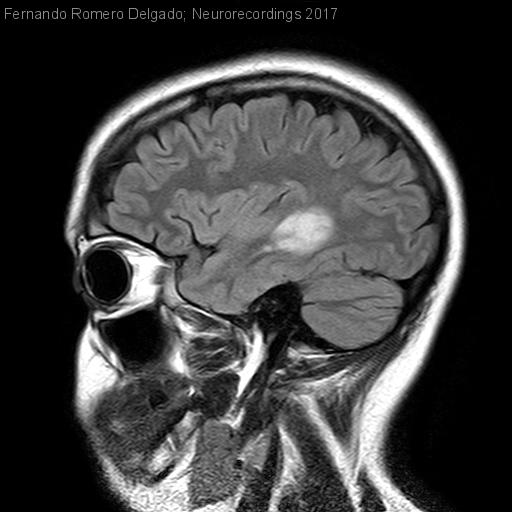

Lesión de apariencia tumefactiva como debut de esclerosis múltiple

Lesión de apariencia tumefactiva como debut de esclerosis múltiple

Mujer | 26 años

Diagnóstico final: Esclerosis múltiple remitente recurrente

Neurología: Enfermedades desmielinizantes

Mujer de 26 años sin antecedentes de interés que presenta dolor retroorbitario derecho de tres días de evolución sin asociar inyección conjuntival ni lagrimeo. Posteriormente comienza con acorchamiento en región malar y hemilengua derecha. Horas...